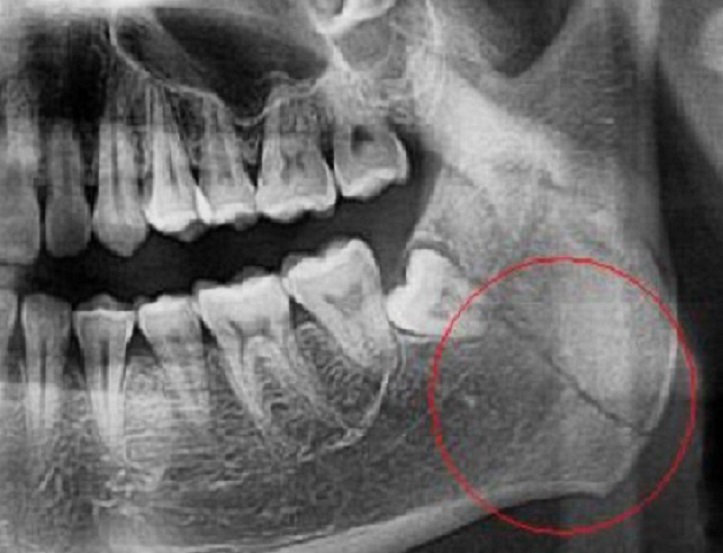

Полицейские выяснили, что вечером в квартире заявителя произошёл конфликт между пострадавшим и женщиной на почве личных неприязненных отношений. В ходе конфликта 41-летняя женщина нанесла мужчине несколько ударов в область лица, в результате чего он получил телесные повреждения в виде открытого двустороннего перелома нижней челюсти со смещением отломков.

Полученные травмы были оценены как причинившие средний вред здоровью.